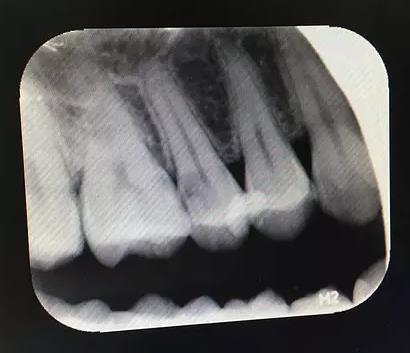

如果隻是近牙髓,但是還沒有感染到牙髓的話,能保髓治療就盡量保髓治療。可以先做牙髓安撫,查看有什麽(me) 反應,如果沒有異常反應,可以保髓,如果安撫有疼痛,可能需要開髓做根管治療。

如果是牙根還沒有發育完全的15歲以前的孩子,通常做保髓治療是比較有價(jia) 值的,而成年後雖然也有人想保住牙髓做保髓治療,但是通常有牙髓炎症,保髓失敗的幾率高,可能還是要做根管治療。

所以保髓治療和根管治療的關(guan) 係就是:保髓是盡量的保留牙髓組織,而根管治療是去除牙髓組織。不過保髓成功後,通常就不需要做根管治療了,需要使用襯墊材料充填補牙就好了。而如果保髓失敗了,說明牙髓炎已經很嚴(yan) 重了,所以殺牙神經做根管治療了。